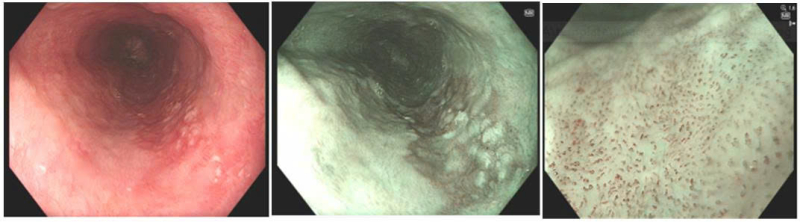

Kết quả nội soi phát hiện tại thực quản cách cung răng trên từ 30cm đến 36cm có tổn thương thay đổi màu sắc kích thước khoảng 2cm x 5.5cm. Dưới phân tích của kỹ thuật nội soi phóng đại và nhuộm màu ảo (NBI) tổn thương có đặc điểm vi cấu trúc mạch máu biến đổi phù hợp với một tổn thương ung thư sớm. Các bác sĩ đã tiến hành sinh thiết tổn thương gửi làm giải phẫu bệnh, kết quả loạn sản độ cao.

Hình ảnh tổn thương ung thư sớm thực quản trên nội soi

Tổn thương ung thư sớm thực quản được cắt bỏ qua nội soi